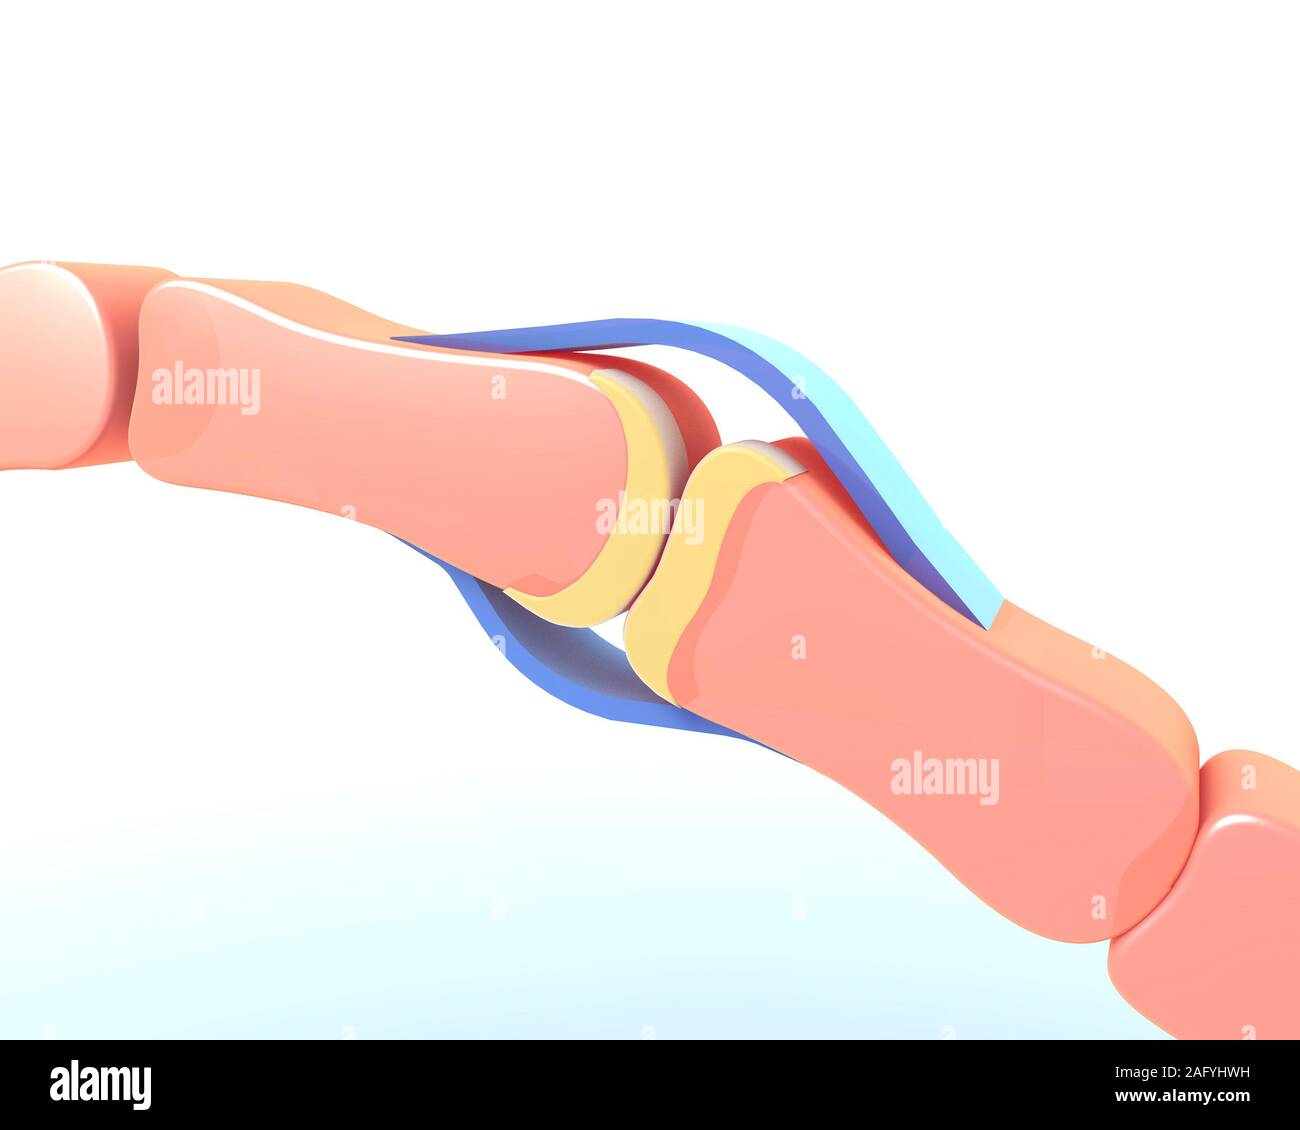

3d illustration of the synovial joint of the bone of a hand. Schematic and symbolic graphic representation. Stock Photohttps://www.alamy.com/image-license-details/?v=1https://www.alamy.com/3d-illustration-of-the-synovial-joint-of-the-bone-of-a-hand-schematic-and-symbolic-graphic-representation-image336823581.html

3d illustration of the synovial joint of the bone of a hand. Schematic and symbolic graphic representation. Stock Photohttps://www.alamy.com/image-license-details/?v=1https://www.alamy.com/3d-illustration-of-the-synovial-joint-of-the-bone-of-a-hand-schematic-and-symbolic-graphic-representation-image336823581.htmlRF2AFYHWH–3d illustration of the synovial joint of the bone of a hand. Schematic and symbolic graphic representation.

3d illustration of the synovial joint of the bone of a hand. Schematic and symbolic graphic representation. Stock Photohttps://www.alamy.com/image-license-details/?v=1https://www.alamy.com/3d-illustration-of-the-synovial-joint-of-the-bone-of-a-hand-schematic-and-symbolic-graphic-representation-image336823590.html

3d illustration of the synovial joint of the bone of a hand. Schematic and symbolic graphic representation. Stock Photohttps://www.alamy.com/image-license-details/?v=1https://www.alamy.com/3d-illustration-of-the-synovial-joint-of-the-bone-of-a-hand-schematic-and-symbolic-graphic-representation-image336823590.htmlRF2AFYHWX–3d illustration of the synovial joint of the bone of a hand. Schematic and symbolic graphic representation.